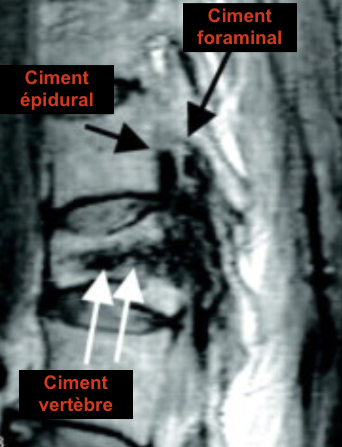

• Risque d’extrusion de Ciment lors des verebroplasties

• Trajets de Vertébroplasties = Pédiculaires, risque de passage intra-canalaire